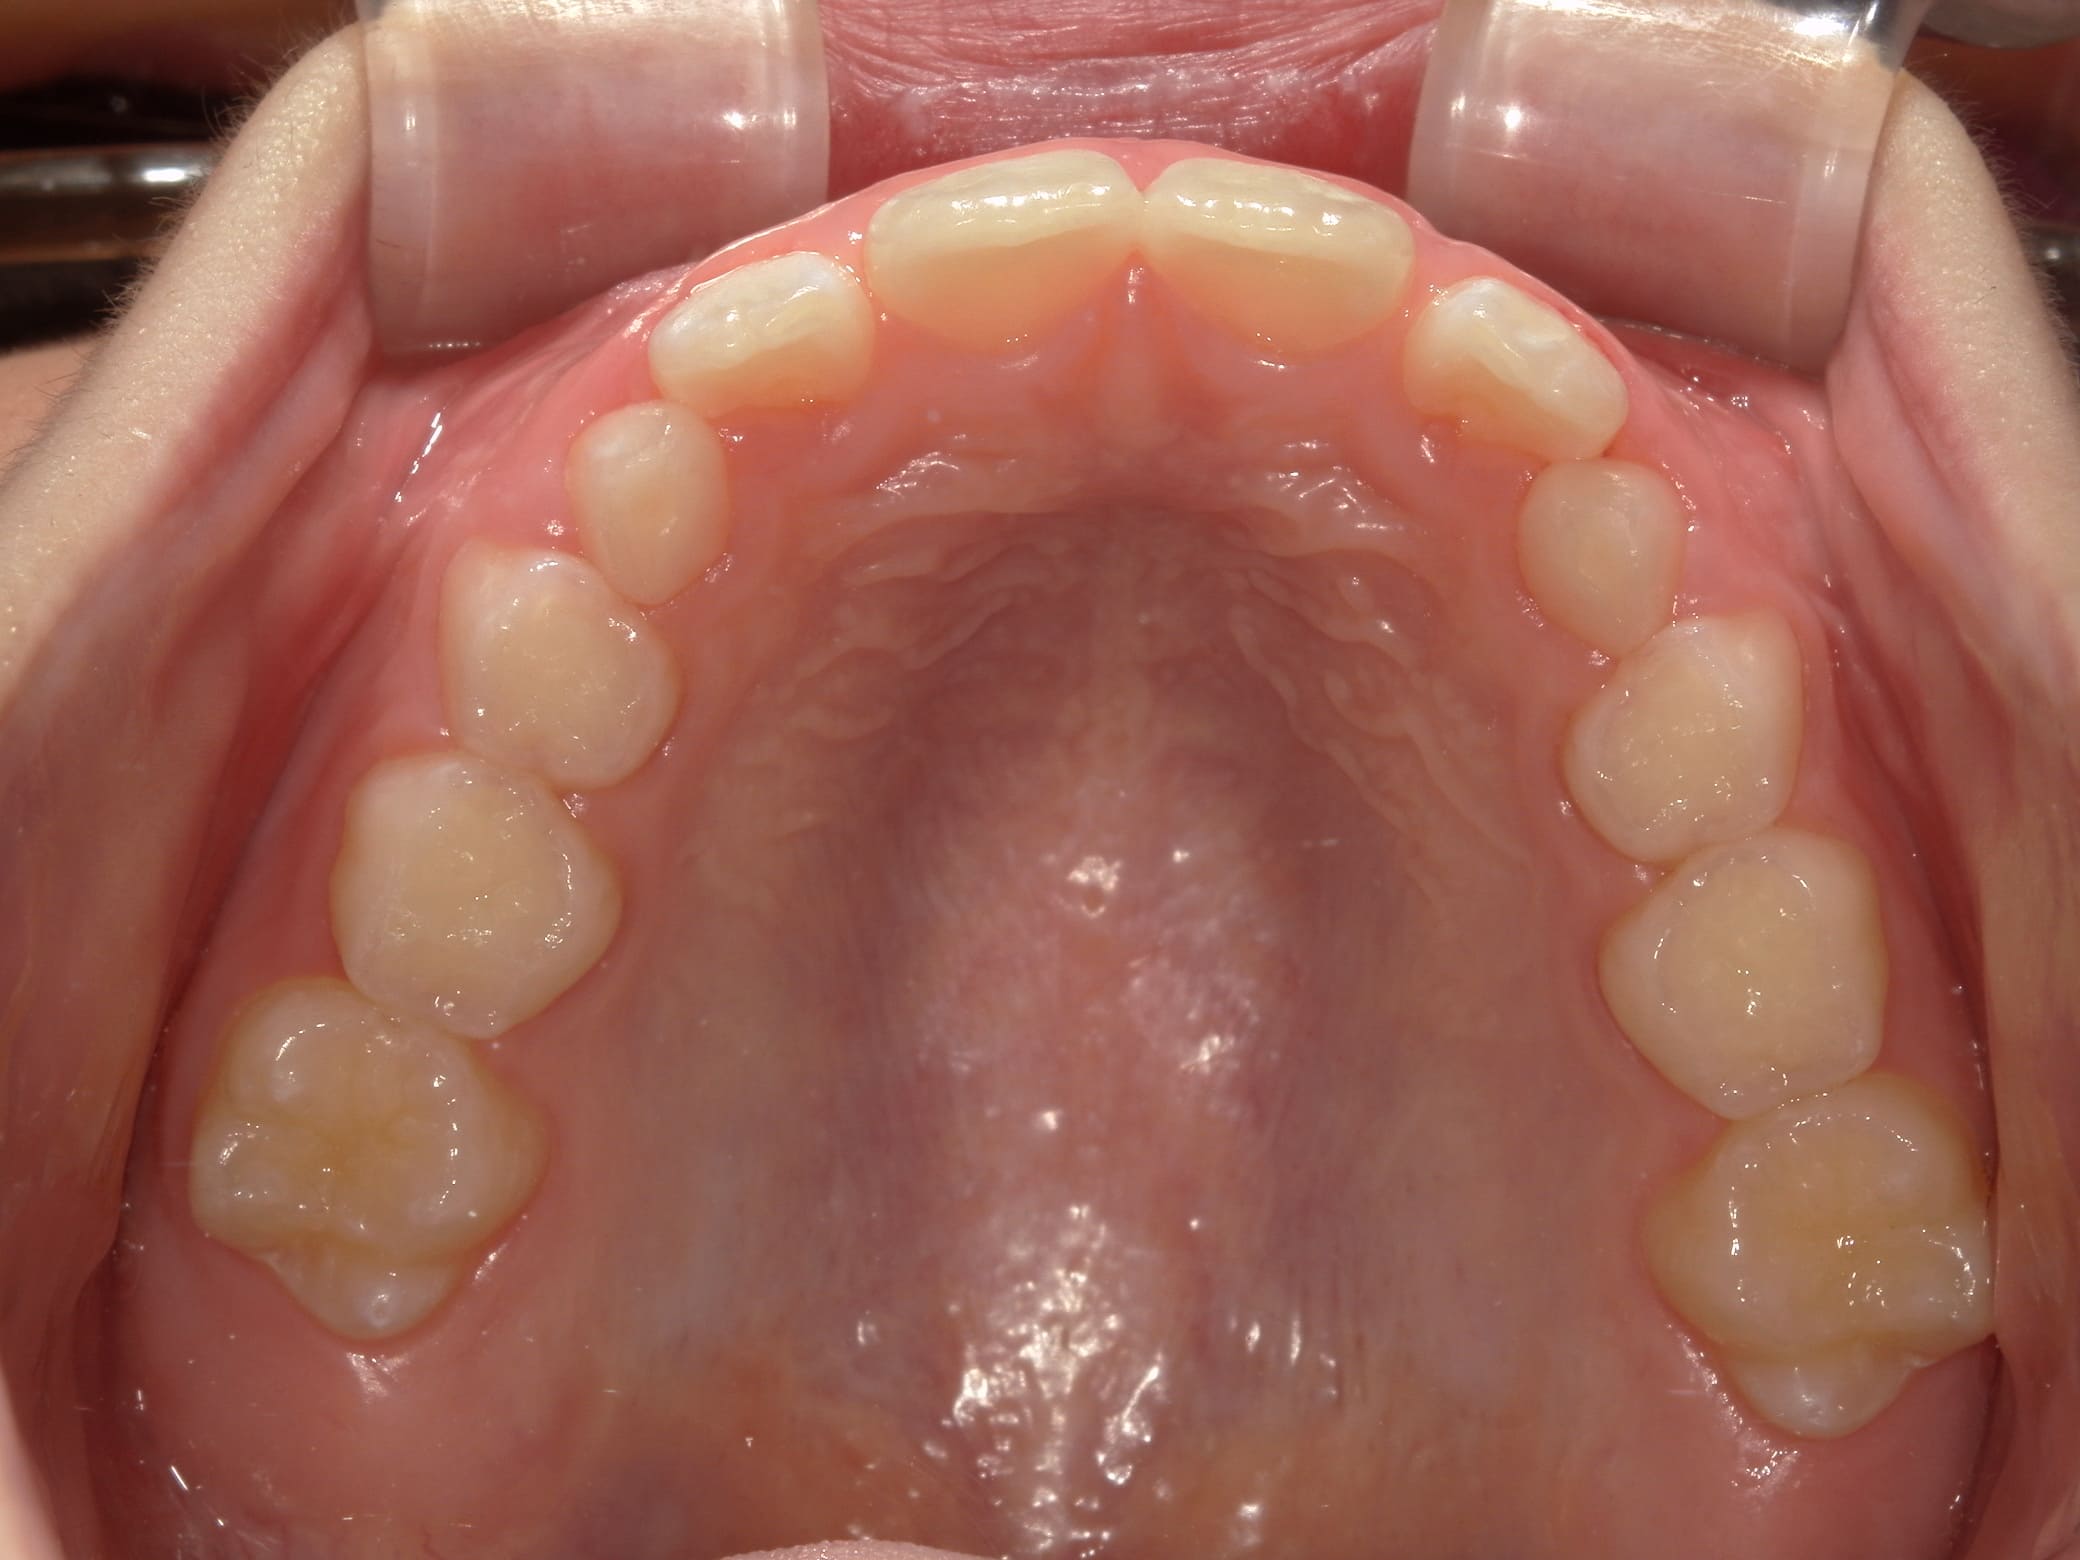

| 年齢・性別 | 8歳9ヶ月の女児 |

|---|---|

| 主訴 | 歯並びの乱れを気にされて来院された患者様です。将来的なスペース不足と歯のねじれ(翼状捻転)が懸念されました。 |

| 治療期間・回数 | 2年10ヶ月・19回 |

| 費用 | 430,000円(税別) |